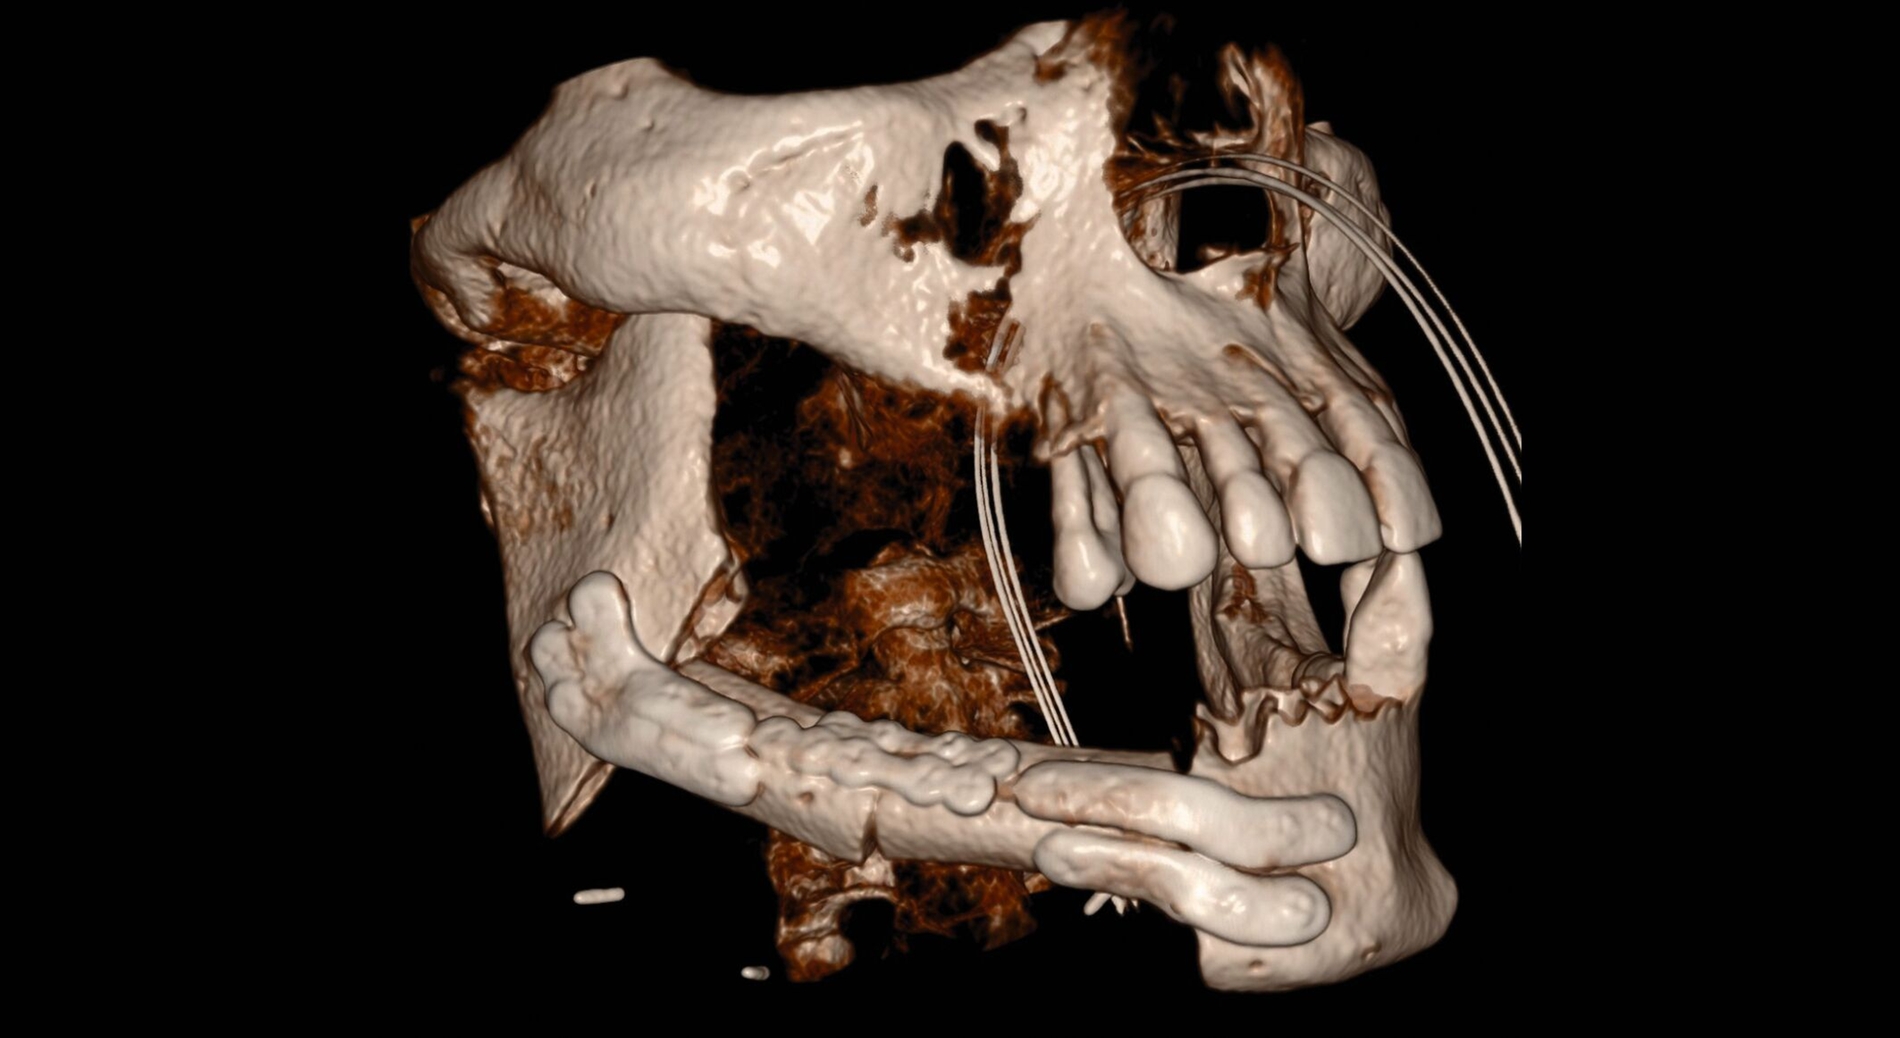

Während sich in den folgenden Jahren vor allem eine rückläufige Läsion mit Verknöcherung des ehemaligen Zystenlumens zeigte, stellte sich der Patient 2024 mit einer plötzlich progredienten Hypästhesie des rechten Nervus alveolaris inferior vor. Bei Verdacht auf Vorliegen eines Rezidivs des bekannten Ameloblastoms erfolgte eine Panoramaschichtaufnahme (Abbildung 1), die den Verdacht erhärtete. Im anschließend folgenden DVT zeigten sich multiple, kreisförmig-zystische Aufhellungen die sich vom Kieferwinkel bis regio 45 erstreckten (Abbildung 2).